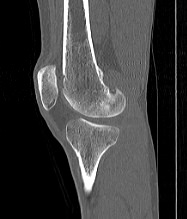

Одним из наиболее информативных методов исследования коленных суставов является мультиспиральная компьютерная томография. КТ относится к лучевым методам исследования и основана на применении ионизирующего излучения с последующей цифровой обработкой данных, полученных при КТ-сканировании.

В наших медицинских центрах обследование коленного сустава проводится на современных мультиспиральных компьютерных томографах последнего поколения TOSHIBA AQUILION. При помощи рентгеновских лучей аппараты послойно сканируют в разных плоскостях исследуемую область с толщиной среза от 0,5 мм. В результате получаются детальные снимки и цифровые трехмерные изображения коленного сустава в мельчайших подробностях. Помимо точности и достоверности диагностики современные компьютерные томографы обеспечивают для пациента минимальную дозу рентгеновского облучения.

Мультиспиральная компьютерная томография дает возможность оценить структуру костной ткани, выявить переломы, воспалительные изменения, участки деструкции костей и диагностировать опухолевые образования. Мультиспиральная КТ часто применяется в ортопедии и травматологии. За счет быстроты, доступности и неинвазивности (то есть обследование выполняется без вмешательства в организм) метод незаменим при травмах сустава, а также при планировании оперативных вмешательств, например, в случае эндопротезирования сустава. В послеоперационном периоде КТ помогает оценить эффективность проведенной операции, вовремя выявить осложнения и отследить процесс восстановления.

Что показывает КТ коленного сустава

- переломы костей;

- артроз;

- артрит;

- скопление жидкости в суставе;

- кисту Бейкера;

- костные наросты на поверхности сустава;

- новообразования

- полные или неполные вывихи — по смещению образующих сустав элементов относительно друг друга;

- деформирующий остеоартроз, ревматический полиартрит

- злокачественную или доброкачественную опухоль

- гемартроз

- абсцесс.